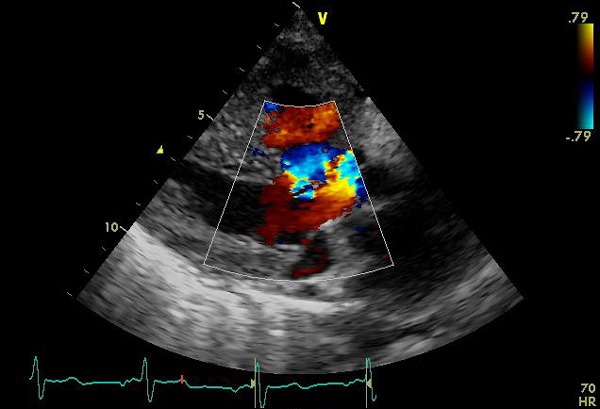

図3: カラードップラー図。収縮期に心室中隔欠損を通じて左室と右室から大動脈に流れる乱流を認める。